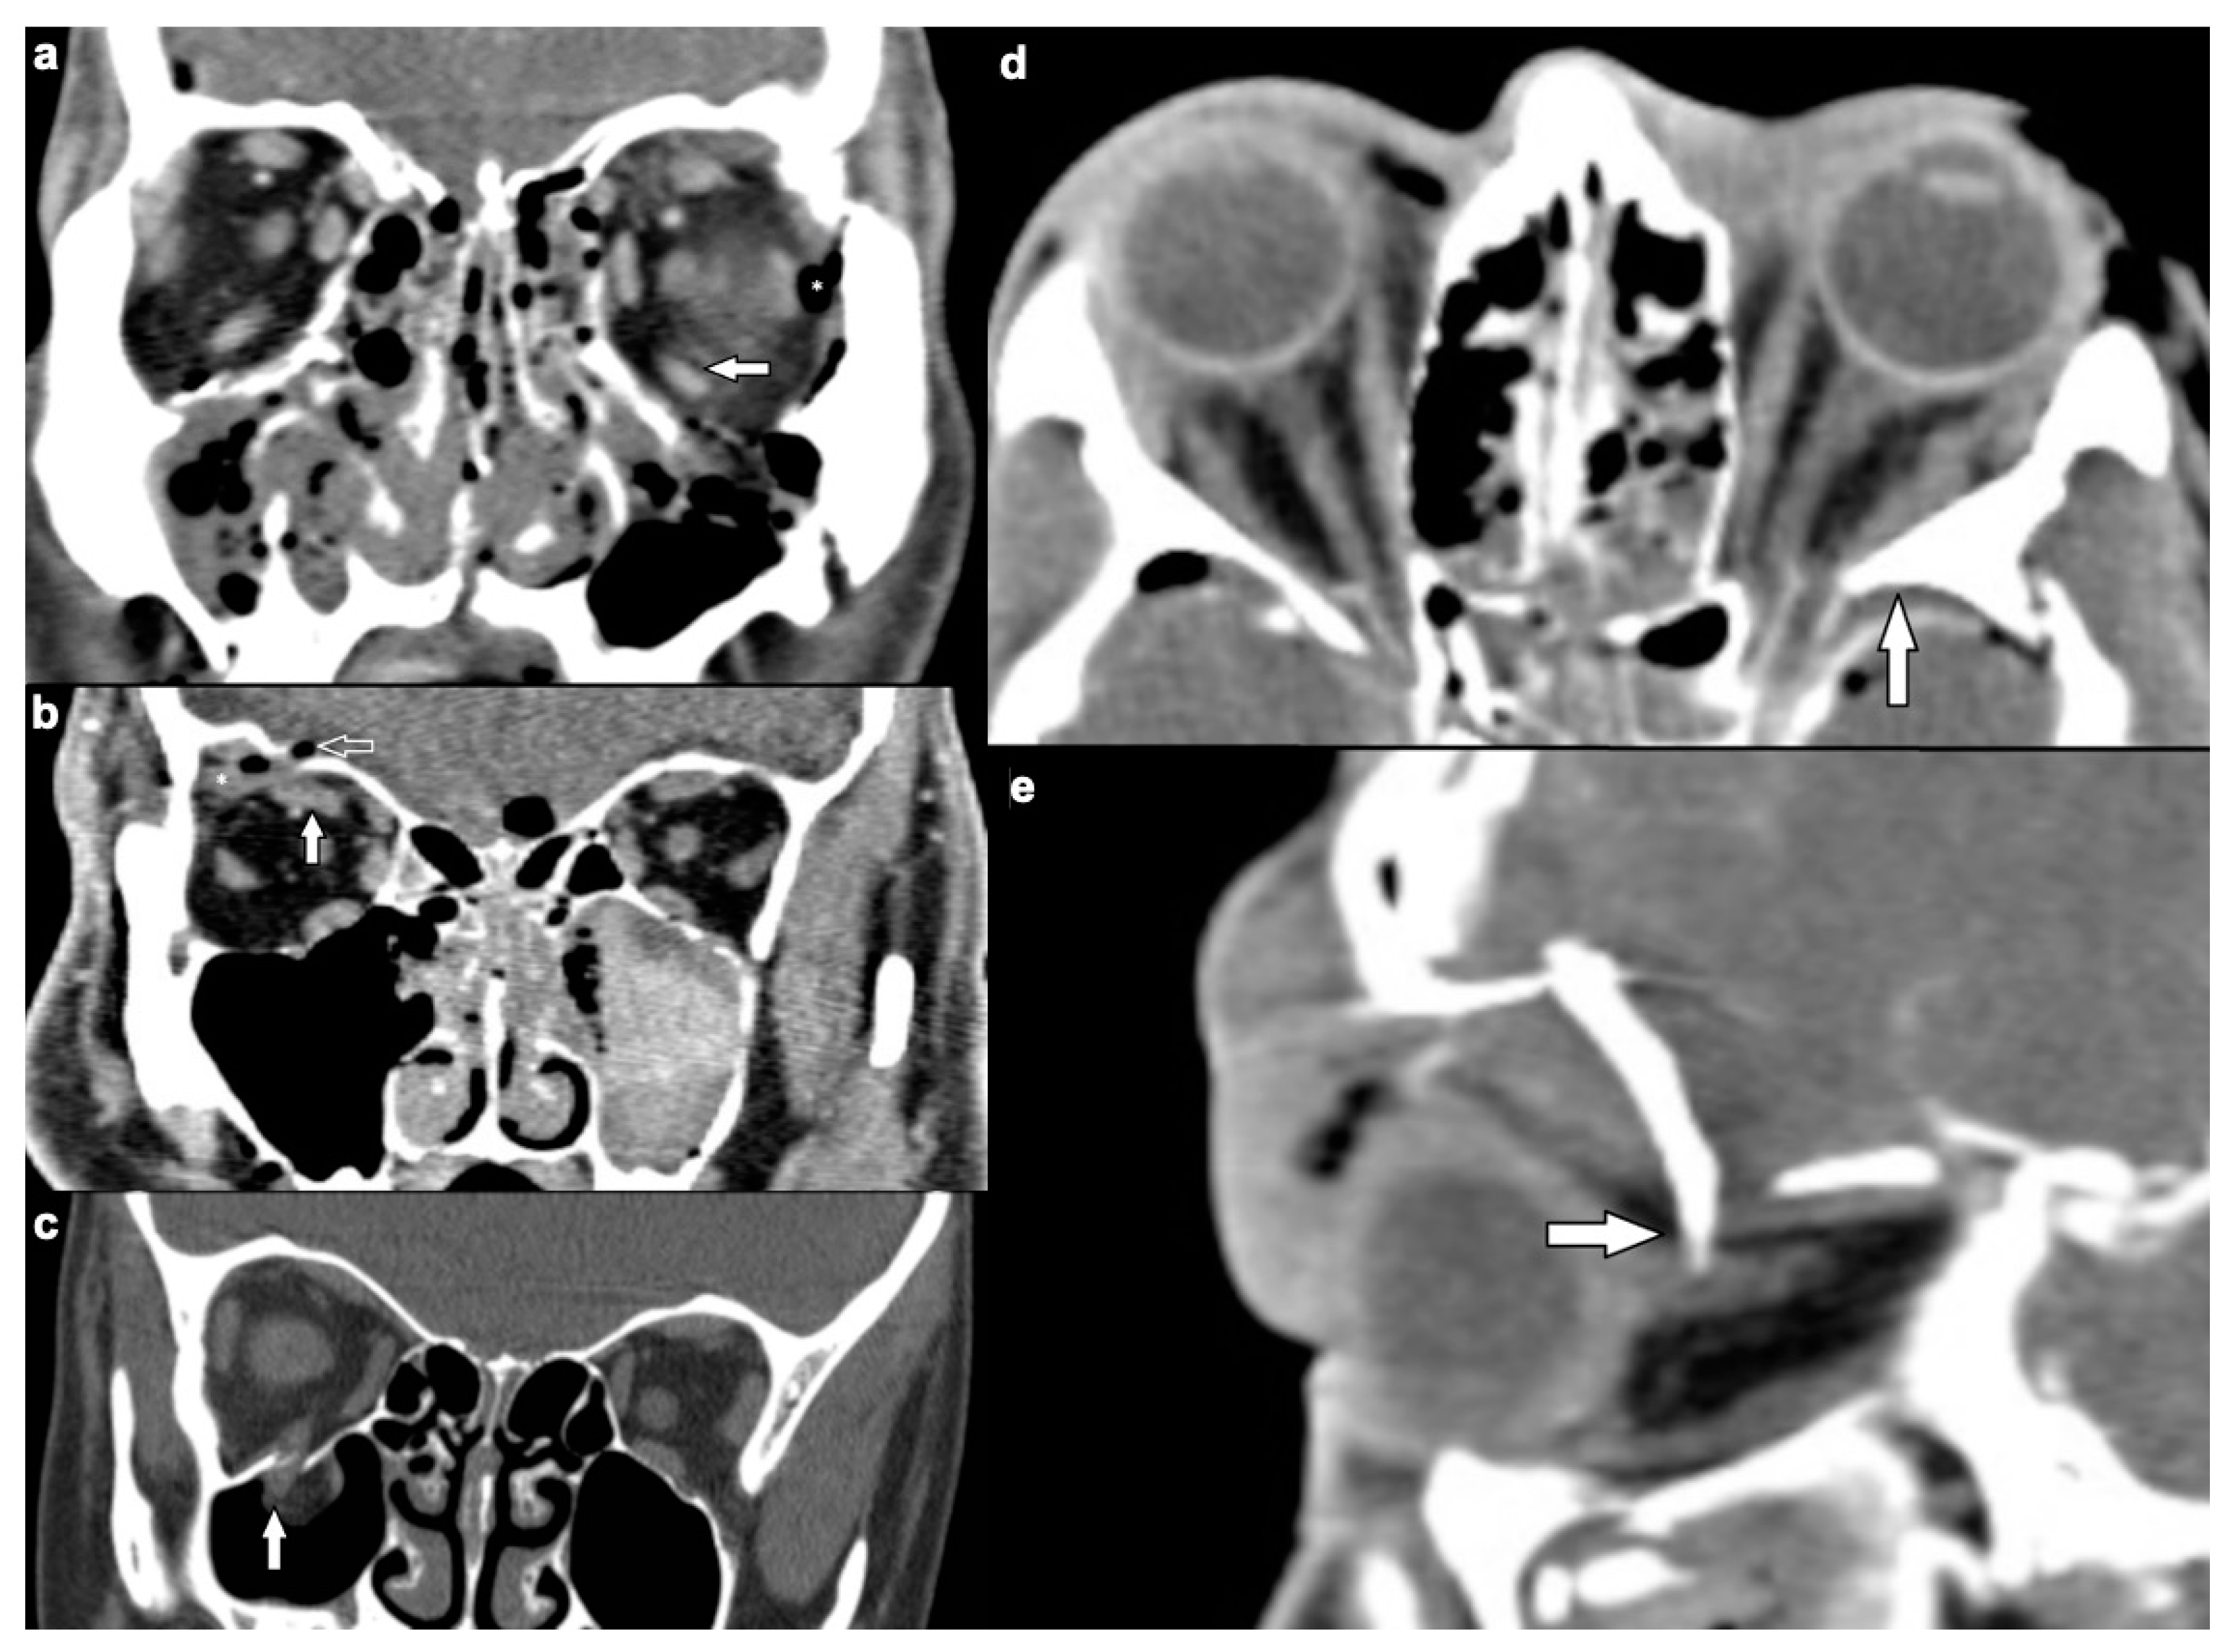

| Extraocular muscles | 54 (53.5) | |

| dislocation | 45 (44.6) | |

| pierced by bone fragment | 8 (7.9) | |

| intramuscular foreign body | 1 (1.0) | |

| Ocular globe and lens | 38 (37.6) | |

| Deformed globe or vitreous body | 24 (23.8) | |

| rupture of ocular globe | 7 (6.9) | |

| dislocated lens | 6 (5.9) | |

| intraconal foreign body | 1 (1.0) | |

| Optic nerve | 24 (23.8) | |

| elongation | 13 (12.9) | |

| otherwise altered morphology | 10 (9.9) | |

| pierced by foreign body | 1 (1.0) | |